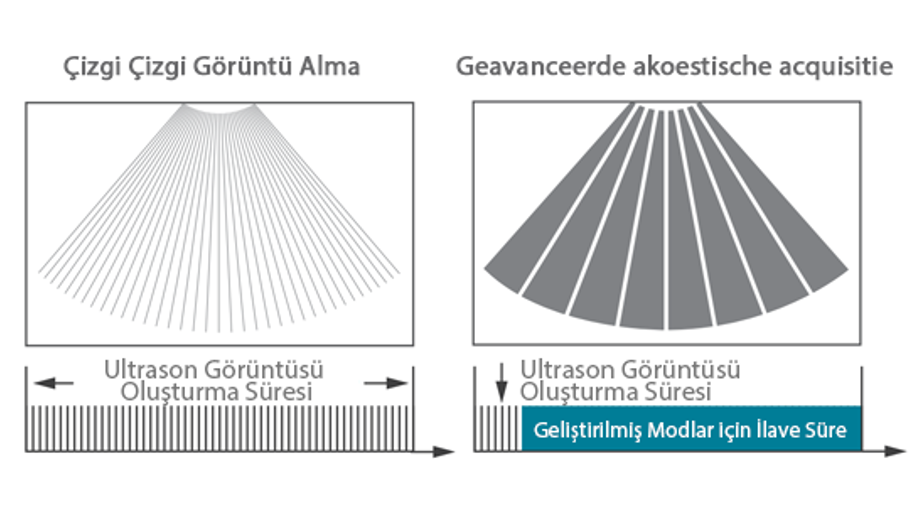

Mindray, ?irketin kuruldu?u gĂŒnden bu yana sĂŒrekli olarak tan?sal do?rulu?u iyile?tirmeye ?al??maktad?r. Devrim niteli?indeki ZONE Sonography? Teknolojisi ile desteklenen Resona 7ânin yeni ZST+ platformu, b?lge g?rĂŒntĂŒsĂŒ alma ve kanal veri i?leme ?zellikleri ile ultrason g?rĂŒntĂŒsĂŒ kalitesini daha ĂŒst bir dĂŒzeye ??kar?yor.